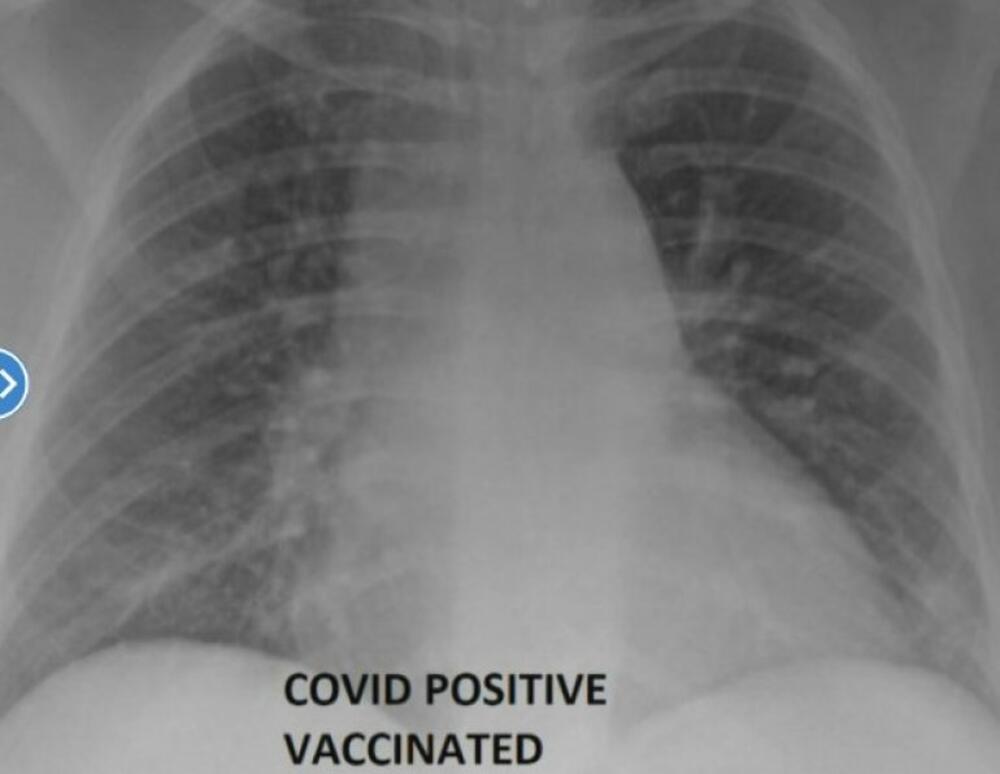

Ove snimke je objavio doktor, koji je prethodno lečio osobe zaražene kovidom, jednu vakcinisanu, drugu ne

Naime, ovi oštri rendgenski snimci otkrivaju razliku koju vakcine protiv kovida čine u odnosu na nezaštićena pluća kada ih napadne virus.

Ove snimke je objavio doktor, koji je prethodno lečio osobe zaražene kovidom, jednu vakcinisanu, drugu ne.

Nasuprot tome, u plućima vakcinisane osobe vazduh struji i izgledaju potpuno očišćena od virusa.